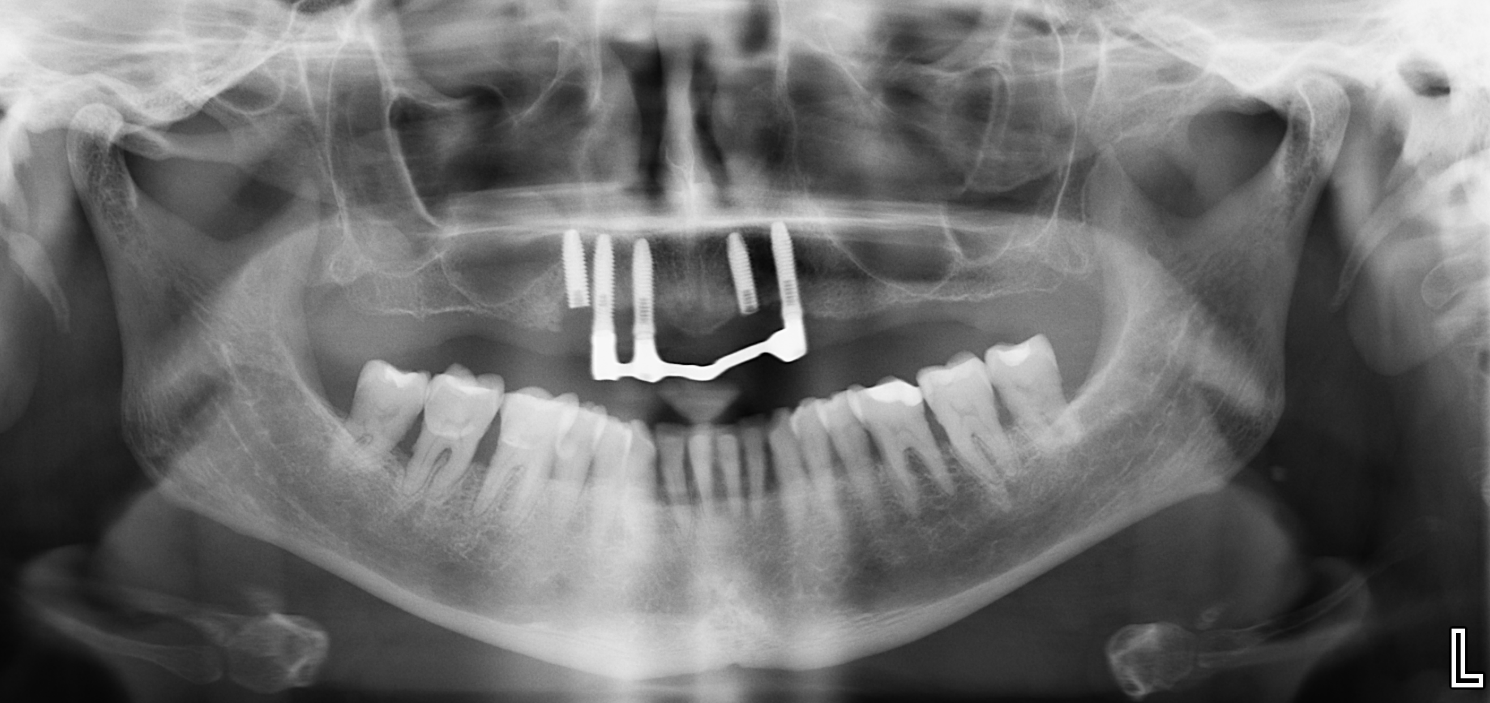

Paciente que hemos decidido extraerles implantes en zona 23 y 24 y queremos saber qué tipo implantes son (marca y conexion).